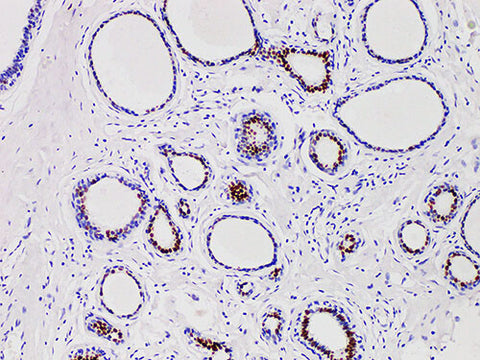

PR Monoclonal Antibody Stored at 2~8°C

Applications IHC-P

Cellular Localization nucleus

Tissue Specificity Breast cancer

Progesterone receptor (PR) has two isomers, pra (94kda) and pRb (114kda), whose function is that transcription factors exist in normal endometrial and mammary epithelial cells after ligand activation. Recently, a large number of studies on breast cancer have shown that most of the ER and PR positive data are effective in endocrine therapy, with high remission rate, low recurrence rate and good prognosis. Even if there is only one positive patient in ER or PR, its prognosis is better than the two all negative patients, so PR has become one of the routine examination items for breast cancer patients.